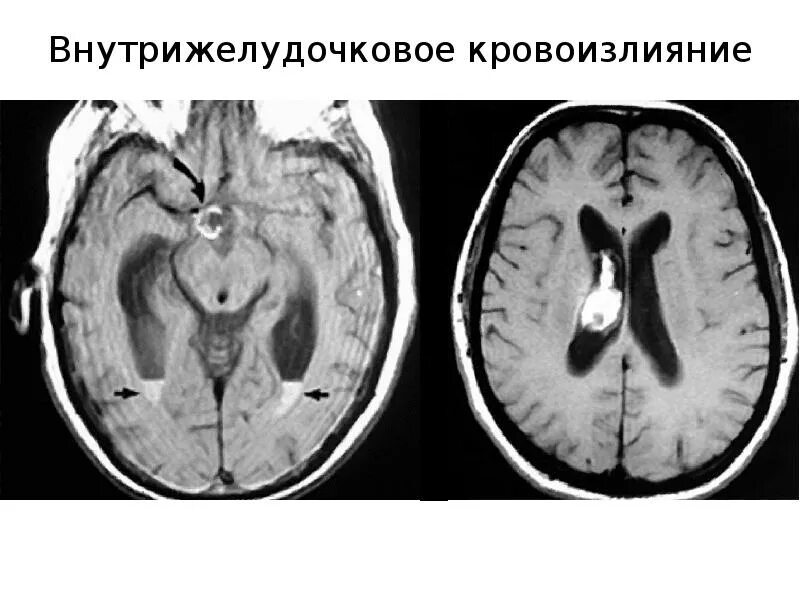

Кровоизлияние в мозг у новорожденного степени